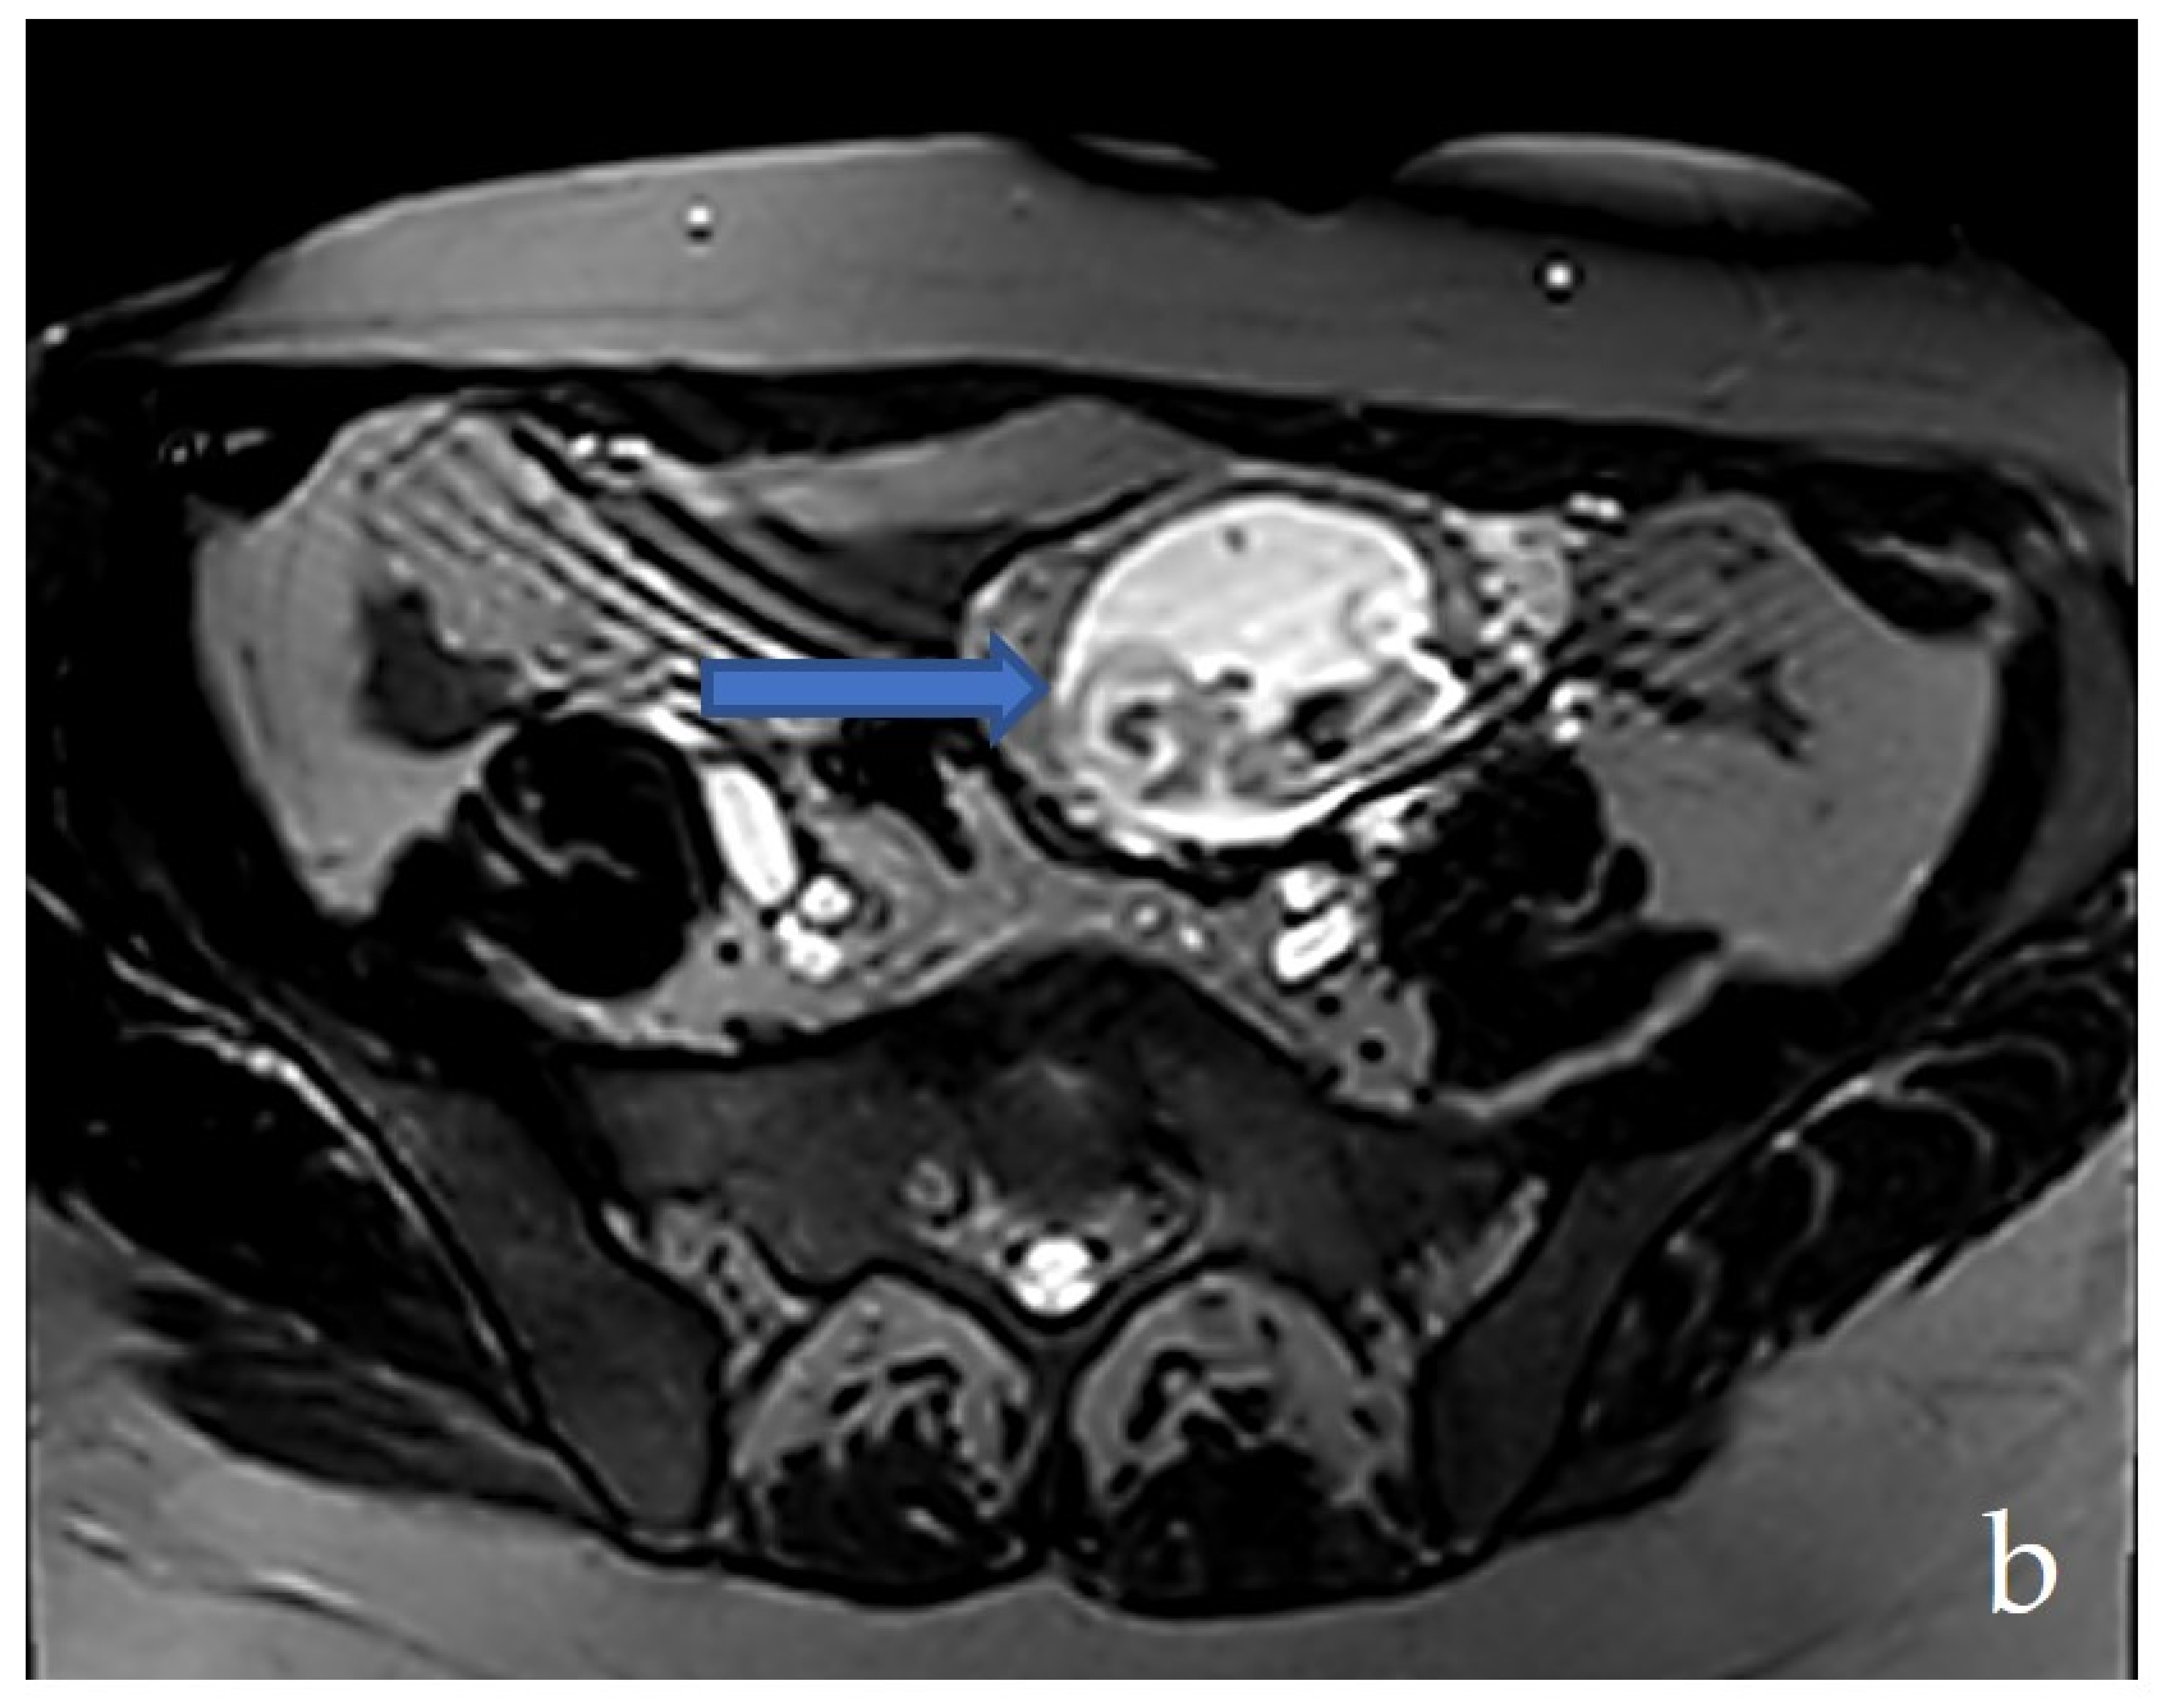

2.3. Diagnostic Assessment and Investigations